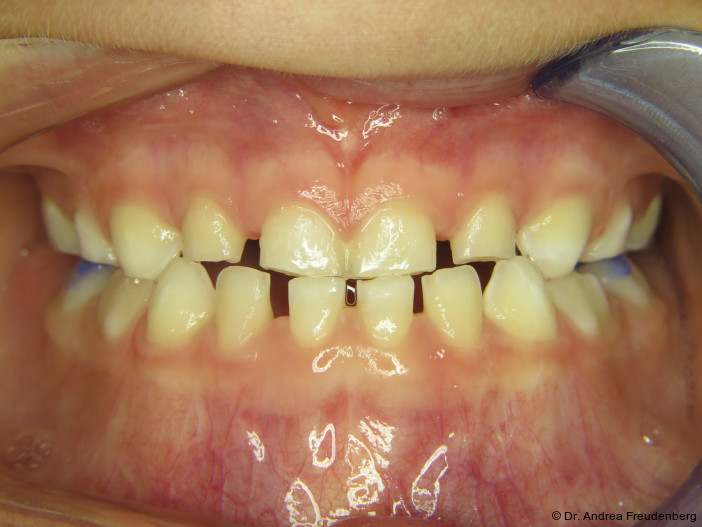

Da Pathologie, d.h. Fehlwachstum, allgegenwärtig ist, möchten wir kurz die physiologische Gebissentwicklung ins Gedächtnis zurückrufen. Ein physiologisches Milchgebiss sollte

- eine halbrunde Form der Zahnbögen,

- eine dezente sagittale und vertikale Frontzahnstufe und

- im Alter von vier bis fünf Jahren Lücken zwischen den Milchschneidezähnen aufweisen (die bleibenden Frontzähne sind ca. ein Drittel breiter als die Milchzähne).

Studien von Grabowski, Stahl und Kundt (2007) zeigen, dass Gebissanomalien vom Milchgebiss (MG) zum Wechselgebiss (WG) deutlich zunehmen. Regelrechte Okklusionsverhältnisse finden sich im MG bei 25 Prozent der Kinder, im WG jedoch nur noch bei 7,3 Prozent. Vergrößerte Overjets treten im MG bei 49 Prozent der Kinder auf und steigen im WG auf 59 Prozent, während seitliche Kreuzbisse von 7,2 Prozent auf 12 Prozent zunehmen.5